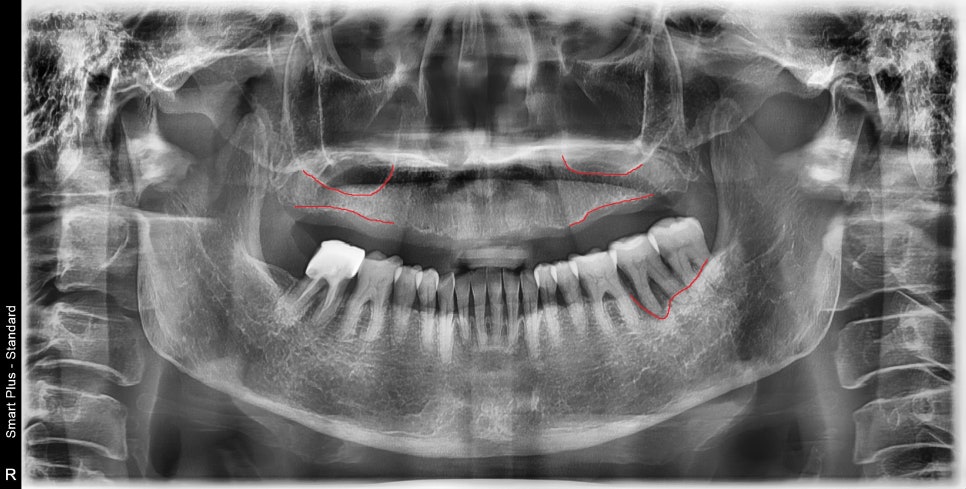

초진 엑스레이 사진입니다.

상악은 무치악 상태이고

하악은 맨 끝 어금니 하나가 치주 질환이 많이 진행되었습니다.

상악의 상악동(=부비동)이라고 하는 공간 때문에

치조골의 높이가 부족해 보입니다.